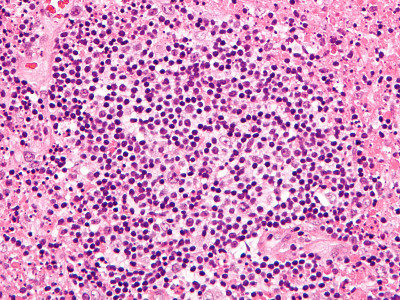

PA:De opbouw van de

lymfklier is verstoord, met folliculaire hyperplasie en necrose van de cortex

en paracortex. Er is een uitgebreid infiltraat van histiocyten met halvemaan-vormige

nuclei, lymfocyten, en immunoblasten. Geen neutrofielen. Soms eosinofielen.

De T-lymfocyten zijn CD8-positief, de histiocyten zijn positief voor CD68, myeloperoxidase,

lysozym, CD163, CD68, en CD4, CD123 is positief in plasmacytoïde dendritische

cellen. De histologische afwijkingen zijn afhankelijk van de fase waarin wordt

gebiopteerd. In het begin (proliferatieve fase) is er folliculaire hyperplasie

en is de paracortex ingenomen door een infiltraat bestaande uit zeer veel lymfocyten,

histiocyten, en T- en B-cel immunoblastaire cellen. Het beeld kan lijken op

een lymfoom. Daarna volgt de necrotische fase met fagocytose van kernpuin en

een voornamelijk histiocytair infiltraat. En tenslotte de xanthomateuze fase

met aggregaten van schuimcellige histiocyten.